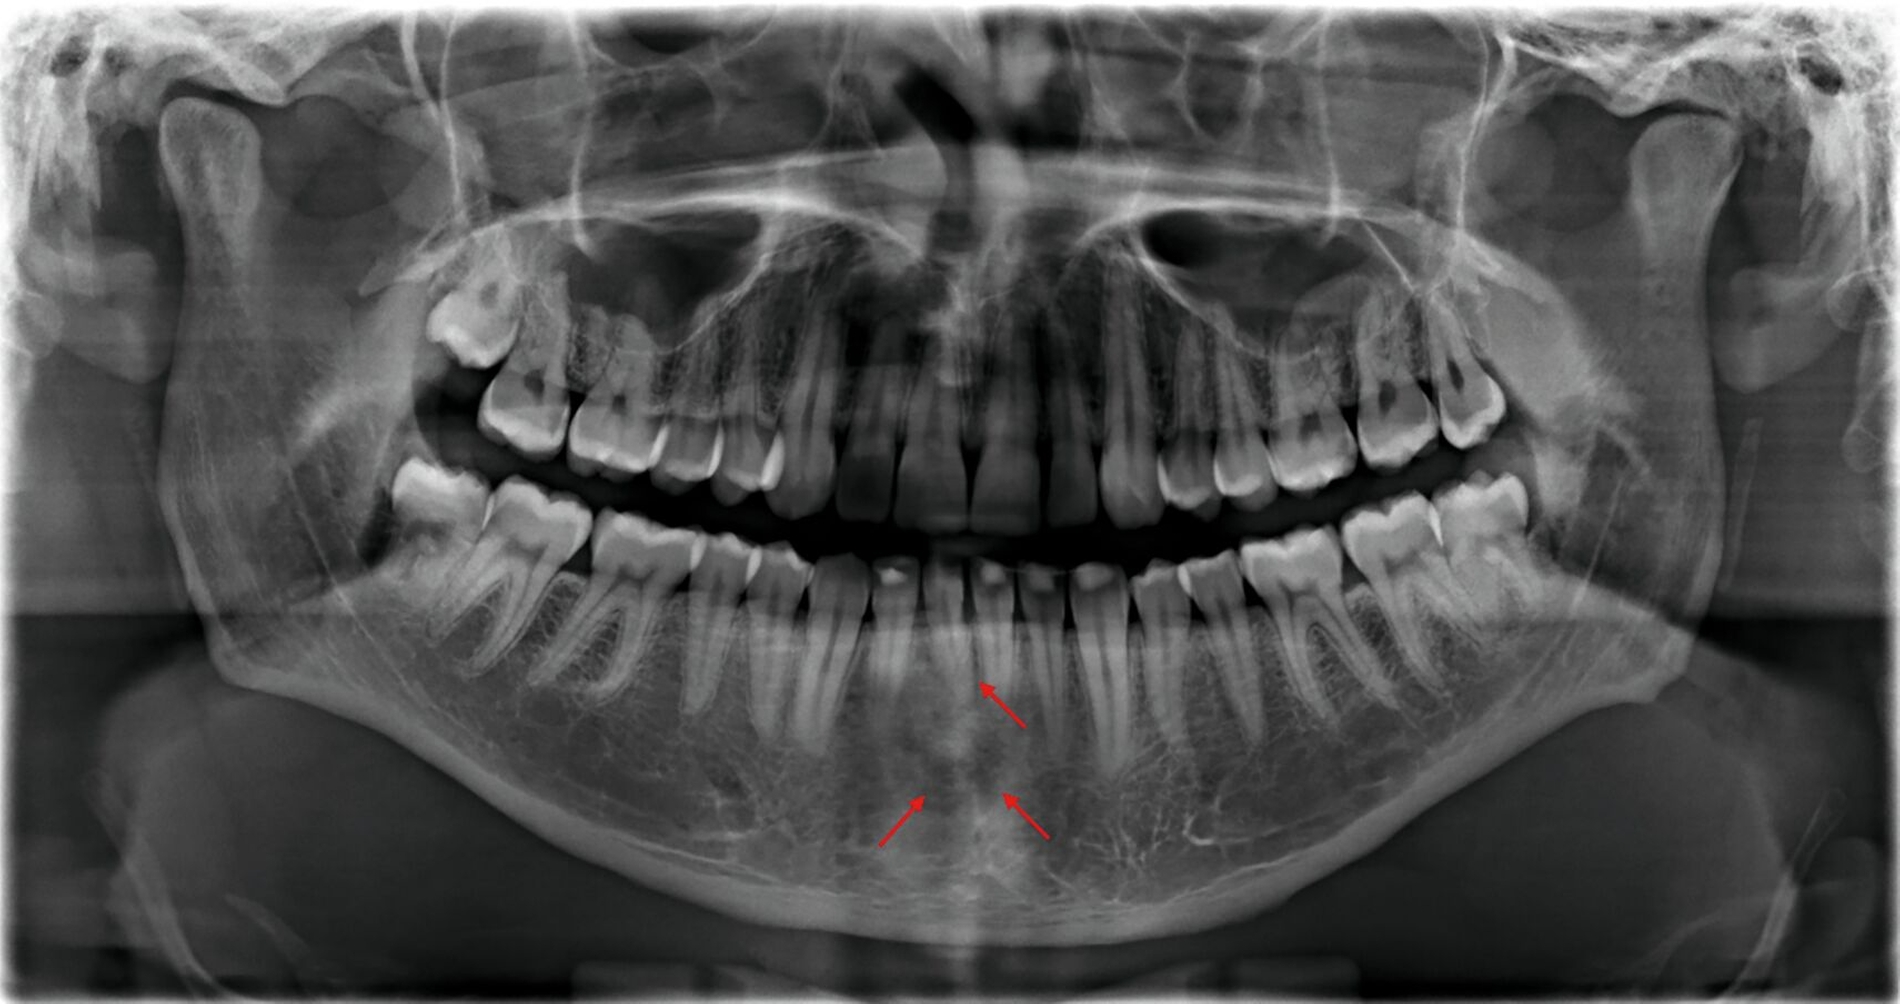

Zunächst wurden Einzelbildaufnahmen der Zähne 24, 26, 35, 33–43 angefertigt. Dabei fiel eine transluzente Frakturlinie ausgehend vom mesialen Parodontalspalt des 41 auf, die sich nach apikal-distal bis zum Apex des 42 darstellte (Abbildungen 3 und 4). Für einen radiologischen Überblick, mit dem auch eine Kiefergelenksfraktur ausgeschlossen werden kann, wurde eine Panoramaschichtaufnahme herangezogen (Abbildung 5). Darauf bildete sich eine unscharfe, C-förmige Transluzenz apikal der Zähne 31 und 41 ab. Eine genaue Beurteilung war nicht möglich, da der Bereich apikal der Unterkieferfront außerhalb der Bildebene lag. Die Processus coronoidei und condylares stellten sich beidseits unauffällig dar. Die Verdachtsdiagnose lautete: Unterkieferfraktur, unkomplizierte Kronenfrakturen an den Zähnen 26 und 35 sowie eine Längsfraktur an Zahn 24.